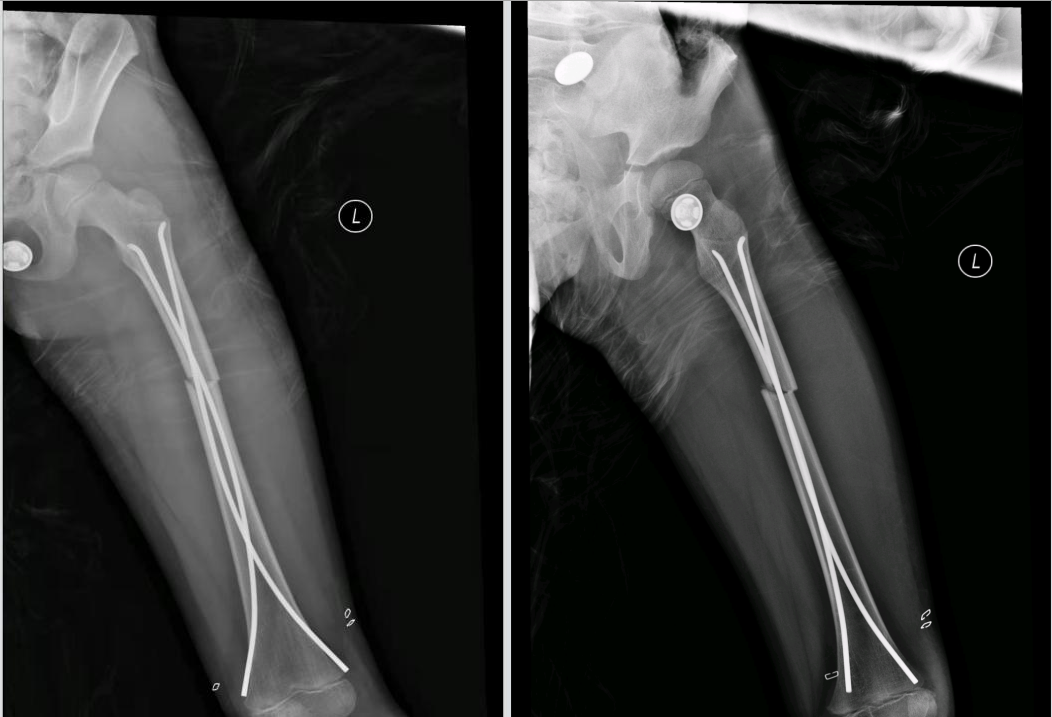

术后片子如下:

弹性髓内钉是一种专门应用于儿童的长骨骨折的内固定物,其特点是能够闭合复位、微创置入,手术后不影响孩子的骨骼发育。该手术减少了对骨膜血运的破坏,保留了血肿内有成骨作用的生长因子,从而更快的促进愈合。并具有三点固定的特点,患儿可以早期功能锻炼和负重。该技术已得到世界范围内小儿骨科医生的广泛推崇,成为治疗儿童长骨骨折的首选方法,并被国际学界誉为--上帝送给骨折儿童的礼物。

弹性髓内钉广泛适用于胫骨、股骨、尺桡骨等长管状骨骨折。通过非常迷你的皮肤切口,在C型臂透视引导下穿入两枚弹性髓内钉,即可起到恢复骨折的对位对线,维持骨折端的稳定的作用。